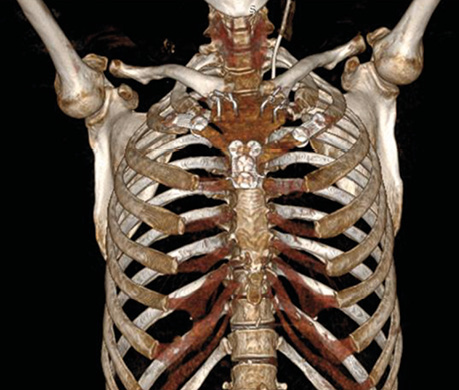

За даними КТ органів грудної клітки візуалізовано пухлинне ураження ручки грудини з внутрішньогрудним компонентом праворуч та поширенням на 2-ге ребро справа (рис. 1).

Рис. 1. КТ органів грудної клітки